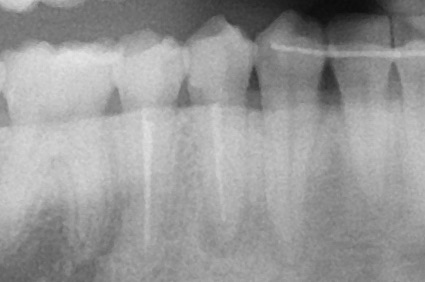

レントゲン

聞くと、10数年前に治療したとのこと。

5番と同じく根尖までキレイに根充材は入っていますが‥

おそらく同じような時期に治療されたのかな?と思います。

通常、根管治療した歯はクラウンにするのが通法ですが。

まだ年齢的に若いし、歯質が残っていたからでしょうね。グッジョブです。